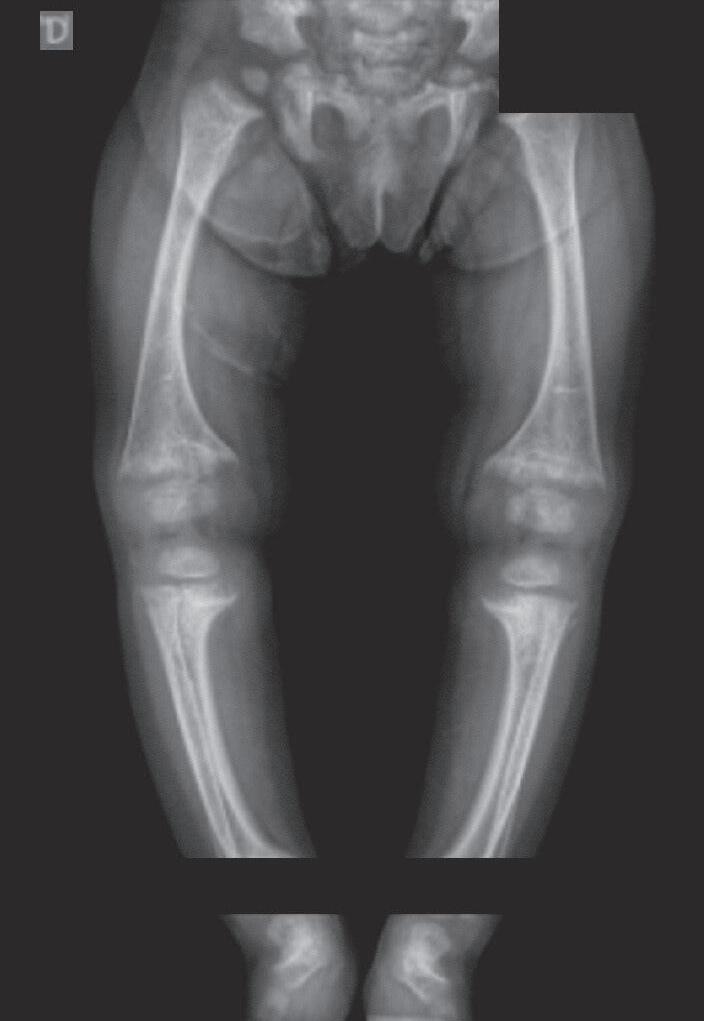

calcificação provisória na interface metáfise/epífise. Posteriormente, ocorre desorganização progressiva da placa metafisária, que se apresenta côncava, alargada, limites irregulares e franjeados, constituindo o sinal da taça (Figura 38.2).

Os achados típicos são rarefação óssea generalizada e alterações na placa de crescimento, que alcançam diferentes graus de gravidade em relação à perda dos limites, franjeamento das bordas metafisárias, concavidade e distanciamento entre a metáfise e a epífise. Na osteomalácia pode haver adelgaçamento da cortical dos ossos longos e pseudofraturas (zonas de Looser), mais frequentes em colo de fêmur, omoplata e púbis.5-7

A gravidade do raquitismo pode ser analisada a partir do escore de gravidade do raquitismo.8 Essa é uma escala de pontos (de 0 a 10 no total) obtida pela análise das alterações radiológicas observadas nas placas de crescimento dos punhos (rádio e ulna distais) e do joelho (fêmur distal e tíbia proximal), avaliando-se o grau de irregularidade, de concavidade e da extensão afetada da placa de crescimento.

Figura 38.2   (A a C) Achados radiológicos característicos em pacientes com raquitismo. Sexo feminino, 8 anos de idade, raquitismo calciopênico por deficiência da 25-hidroxilase (mutação no gene CYP2R1), observa-se alargamento das junções costocondrais (rosário raquítico) (A ). Sexo feminino, 2 anos de idade, raquitismo hipofosfatêmico ligado ao X (mutação no gene PHEX), observam-se rarefação óssea difusa, placas de crescimento dos membros superiores e inferiores com limites mal definidos, alargadas; metáfises distais do rádio e ulna com bordas côncavas (sinal da taça) e maior distanciamento entre metáfise e epífise (B e C)

Fonte: imagens pertencentes ao autor.